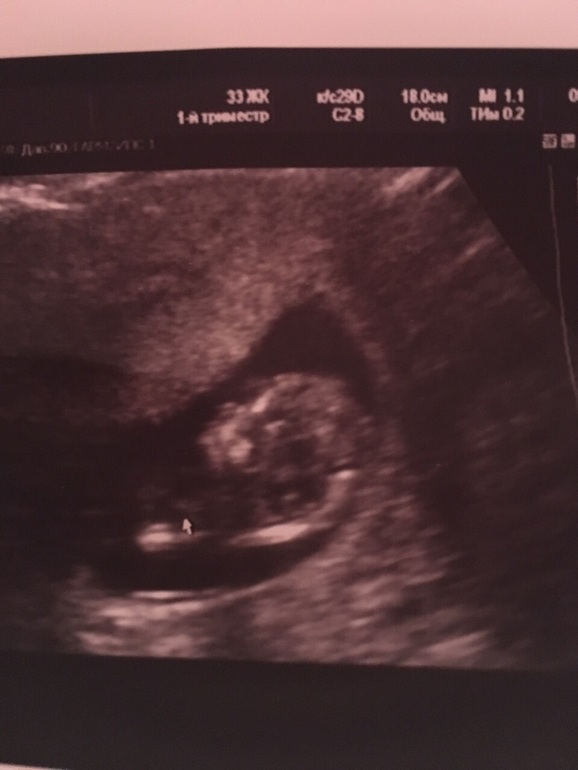

Наше УЗИ в 11+3

Вот и сходили мы на первый скрининг:) "официальный " еще впереди, 15.9

Все у нас хорошо, по УЗИ опережаем на неделю:) замеры:ктр60мм

Сердцебиение 154/мин

ТВП1,4

Фотку с во весь" рост" не сделали , но Узистка сказала мальчик :)

И еще опережает по размерам , сейчас 11.3 ,по УЗИ 12+2. Обычно у меня опережать начинали с 20 нед